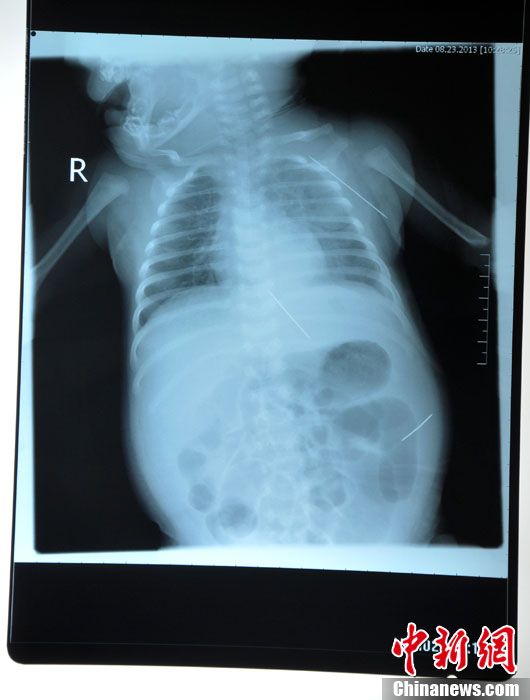

8月23日,黑龙江被“缝衣针”扎伤女婴在哈尔滨医科大学附属第一医院进行手术,成功取出三根长达4.5厘米的缝衣针,目前患儿正在术后观察中,尚未脱离危险期。图为三根钢针在婴儿体内的各个位置。(哈尔滨医大一院供图)中新社发